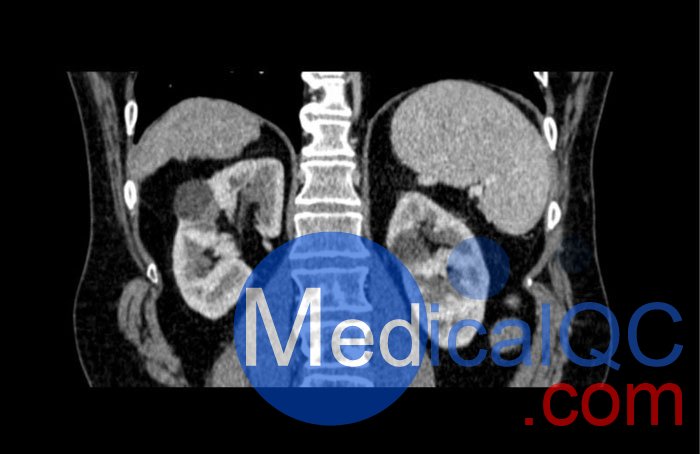

WEK53-04肝硬化腹部模體,WEK53-04腹部模體代表膽囊切除術(shù)后的腹部,帶有小夾子。肝臟有肝硬化的典型體征,在第三腰椎水平植入下腔靜脈過濾器。兩個腎臟都有囊性病變,左側(cè)有一小塊腎結(jié)石。

真實模擬脈管系統(tǒng)、骨骼和軟組織,包括肝臟、胰腺、脾臟、腎上腺、腎臟、胃、小腸和結(jié)腸。

• 肝硬化

• 腎囊腫

• 腎結(jié)石